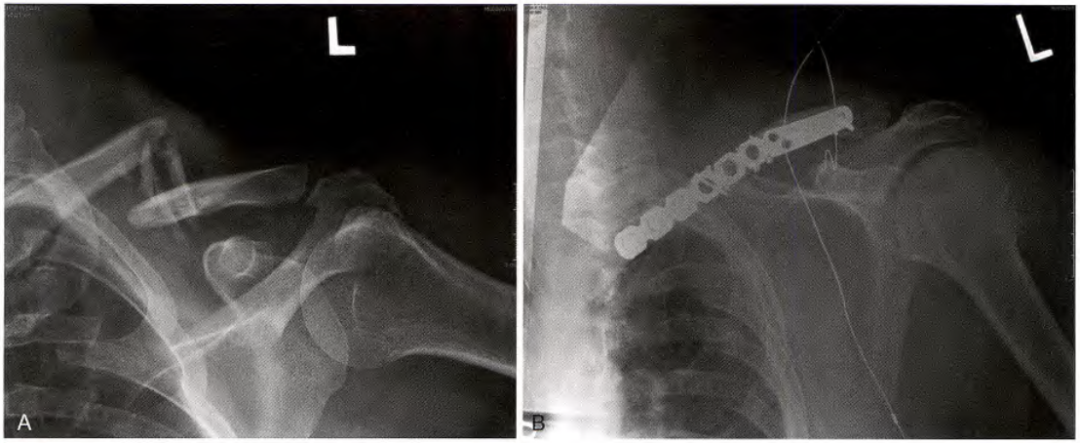

钢板和螺钉固定

A.锁骨骨折, B.前方钢板固定

双微型碎片钢板

锁骨骨折的切开复位内固定

前下方钢板和螺钉固定